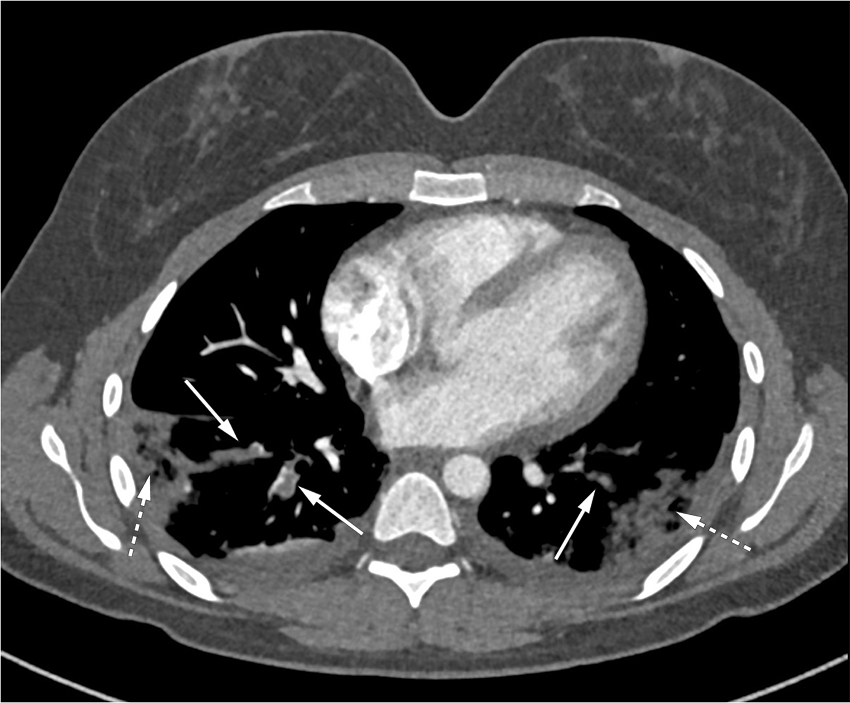

Ved undersøkelse i mottak var hun medtatt, normotensiv og lett takykard, med puls 100–110 slag/min. Ved palpasjon ble det funnet lett forstørrede lymfeknuter i aksillene bilateralt. Hematuri (3+) og proteinuri (3+) ble påvist på urinstiks. Blodprøver tatt ved innkomst er gjengitt i tabell 1. På grunn av dyspné, ble det umiddelbart tatt CT toraks med pulmonal angiografi, som viste lungeembolier i segmentale og subsegmentale arterier (figur 1). Forhøyet D-dimer, lett leukocytose og forhøyet CRP kunne forklares av lungembolifunnet, mens proteinuri og hematuri tydet mer på annen sykdom med nyreaffeksjon.

Klinisk ble pasienten undersøkt med tanke på malignitet. CT-undersøkelse av toraks og abdomen påviste de kjente lungeemboliene, men viste ingen tegn til nyrevenetrombose eller andre tromboser. Det ble ikke påvist forandringer i noen organer som ga mistanke om malignitet. Mammografi gav ingen holdepunkt for tumor. Gynekologisk undersøkelse viste normale funn.